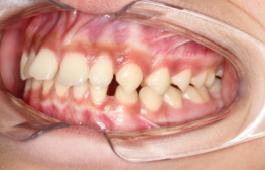

❸ 牙齿不齐:影响咬合关系,影响美观。

前

后